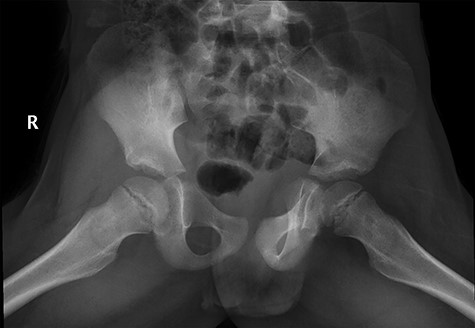

CT hips reported a well-defined lesion seen bilaterally in the neck of femur anterior infero-medial aspect, more prominent on the left side measuring 7 x 3 mm on left side both in coronal (Fig. 3) and axial (Fig. 4) views. On the right side, other lesion measuring 2 x 1 mm (Fig. 5) seen in coronal view. These two lesions are well defined with a sclerotic border with a small cortical defect. The lesion shows fat density. The symmetrical appearance of the lesion combined with the fat density and location suggest the diagnosis of synovial herniation pit. MRI Pelvis revealed minimal left hip joint effusion with loculated fluid seen along the trochanteric bursa with the largest measuring 0.9 x 1.5 cm (Fig. 6, 7).

Showed axial cut of CT hips demonstrating the synovial pit on left and right side.

Follow-up X-ray showed regression of the lesion in the form of progression of the dense sclerosis of the defect of the left femur while the right femur neck lesion is barely visible (Figure 10) and advised for watchful waiting.